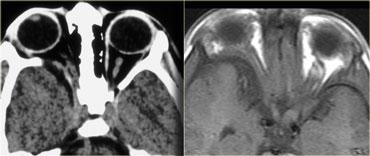

Hình bên trái là hình ảnh của một bệnh nhân nhập cấp cứu với tình trạng sưng nề hốc mắt sau chấn thương.

Bệnh nhân này bị vỡ nhãn cầu, cụ thể là vỡ tiền phòng.

Là các bác sĩ chẩn đoán hình ảnh, chúng ta thường chú ý đến dịch kính khi nghi ngờ vỡ nhãn cầu, nhưng như vậy là chưa đủ.

Lưu ý rằng độ sâu của tiền phòng bị giảm.

Có tình trạng tăng tỷ trọng ở phía trước do xuất huyết tiền phòng (hyphema – máu trong tiền phòng).

Cũng cần lưu ý rằng thủy tinh thể bên phải bị mờ và giảm tỷ trọng nhẹ.

Đây được gọi là đục thủy tinh thể do chấn thương.

Có thể bạn sẽ kỳ vọng thủy tinh thể tăng tỷ trọng hơn, nhưng thực tế thường không phải như vậy.

Hình bên trái là hình ảnh CT của một bệnh nhân bị chấn thương mắt trái.

Hãy phân tích hình ảnh để tìm 5 dấu hiệu trước khi tiếp tục đọc.

Các dấu hiệu bao gồm:

- Tiền phòng nông hơn so với bên phải, gợi ý vỡ nhãn cầu.

- Tỷ trọng trong tiền phòng tăng, gợi ý xuất huyết tiền phòng (hyphema).

- Tỷ trọng của thủy tinh thể giảm, cho thấy bệnh nhân bị đục thủy tinh thể do chấn thương.

- Có vùng tăng tỷ trọng trong buồng dịch kính, gợi ý xuất huyết dịch kính.

- Nhãn cầu dẹt ở mặt sau, cho thấy có vỡ dịch kính kèm theo.

Vỡ nhãn cầu thường gặp nhất ở vị trí tiền phòng.